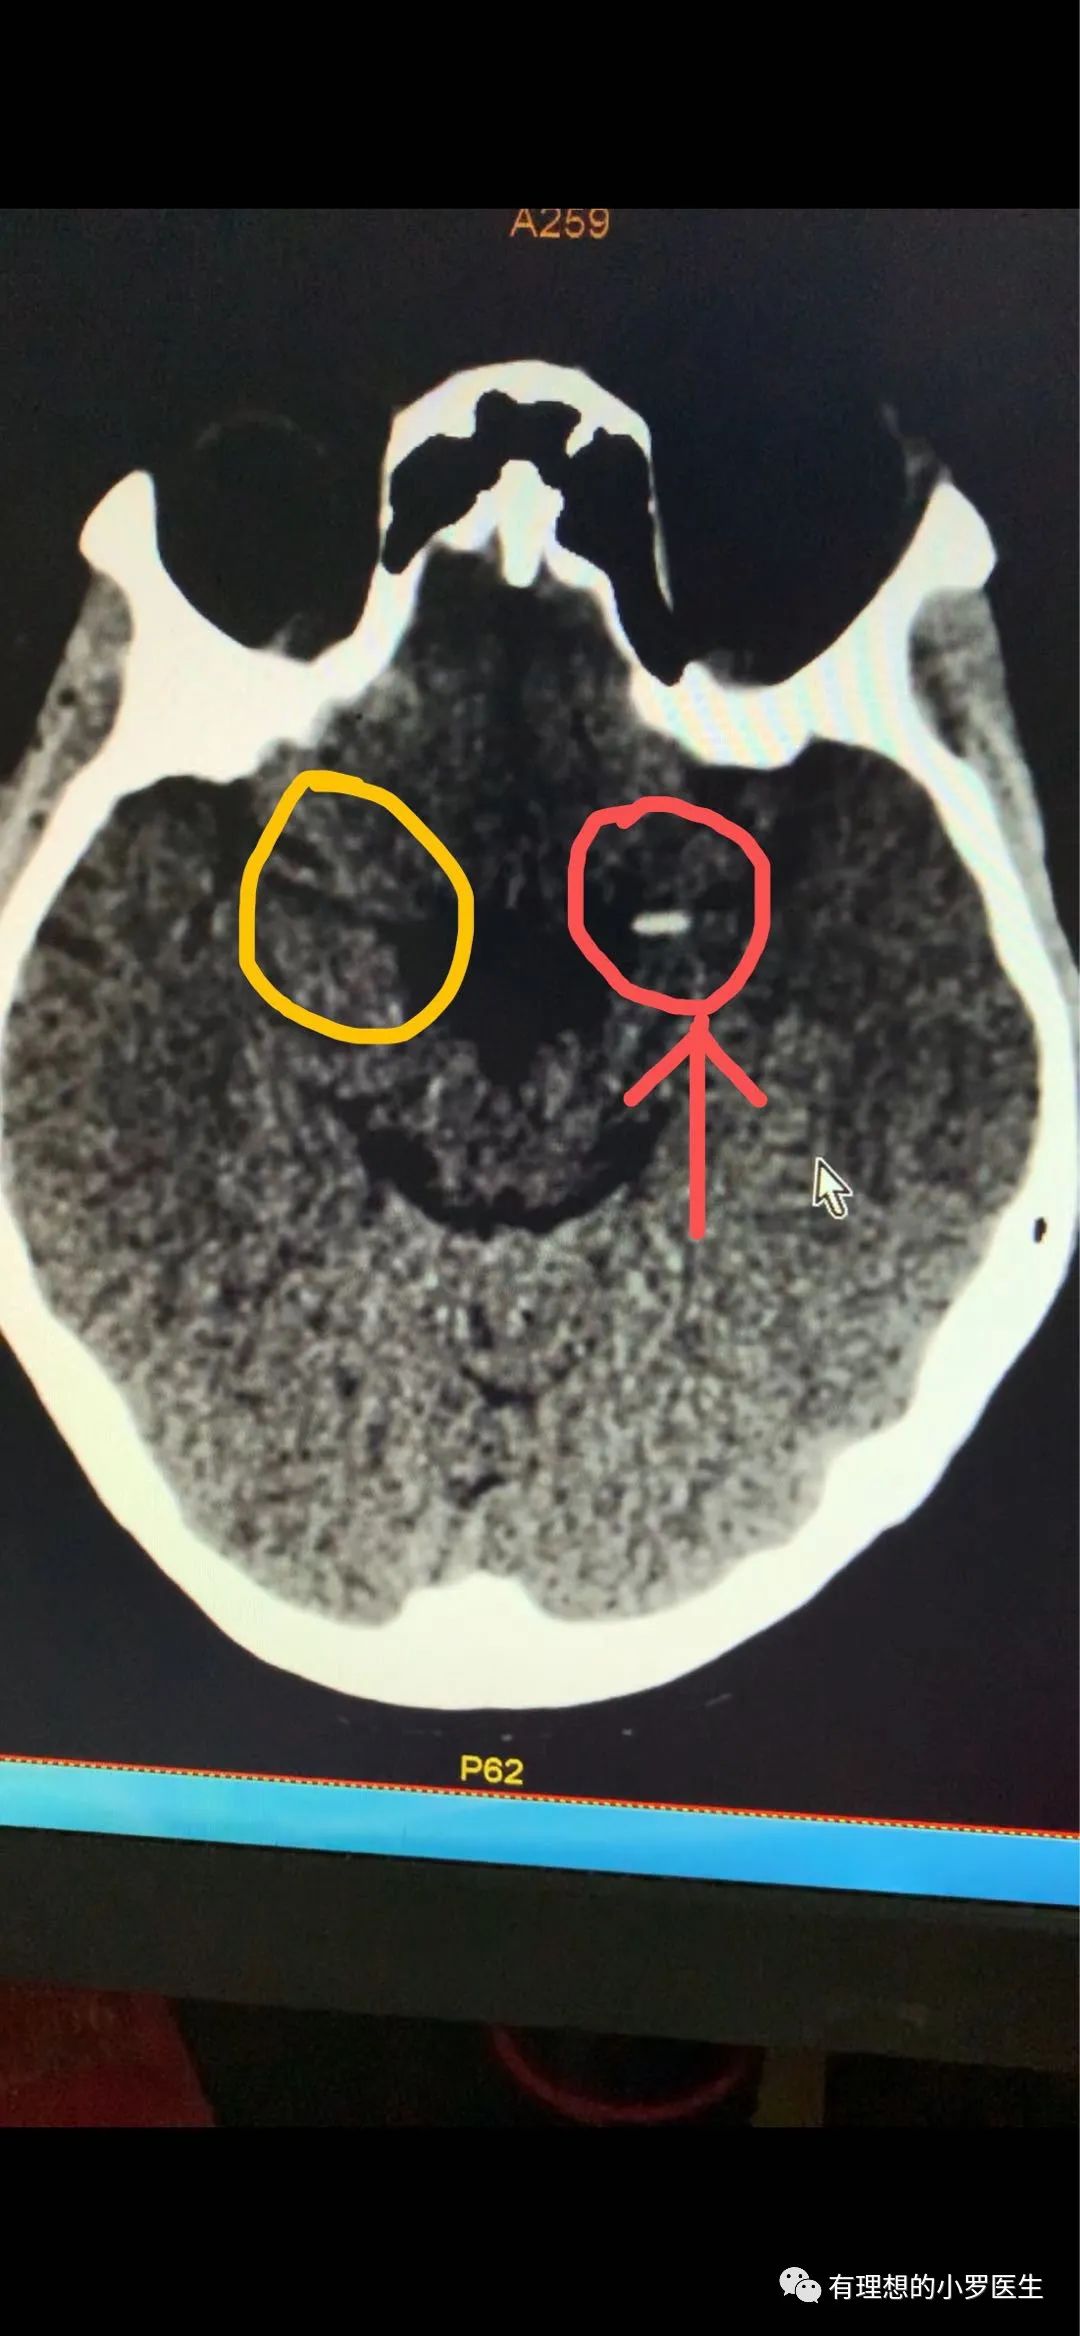

完善头部CT后则与我们的推断相符合,左侧大脑中动脉可见明显的血栓影,左侧大脑可见稍许水肿。

左侧红色标注位置可见明显白色血栓影